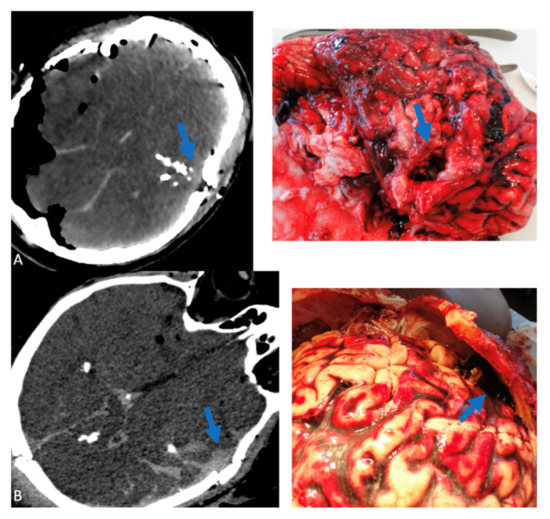

Figure 1, Figure 2 and Figure 3 show correlations between CT scan data and autopsy photographs.

Figure 3. Correlations between CT scan and autopsy concerning abdominal lesions (arrows), (A) right colon and right kidney lesions, (B) lesion of the head of the pancreas, (C) liver lesion.